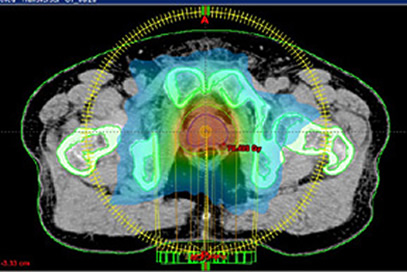

高精度放射線治療にも対応した外照射装置2台(VARIAN社製、CLINAC-iX、CLINAC-21EX)、小線源治療装置(RALS)を運用しています。

大学附属病院という特性上、強度変調放射線治療(IMRT)や体幹部定位放射線治療(SBRT)などの高精度治療に重点を置いて治療を実施しておりますが、もちろん緩和的な放射線治療を含め、一般的な放射線治療も積極的に丁寧に実施しています。